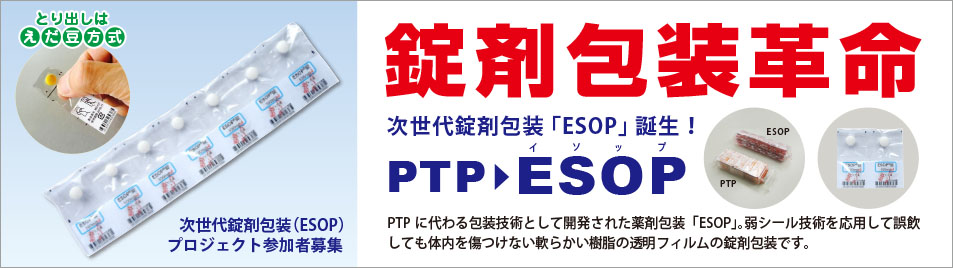

Http Www Morimoto Iyaku Jp Wp Content Img Sympo Downloadpage Esop Shoukai 151221 Pdf

錠剤を包装する Ptpシート の高機能化が進む事情 ニュースイッチ By

Http Www Morimoto Iyaku Jp Wp Content Img Sympo Downloadpage Esop Shoukai 151221 Pdf